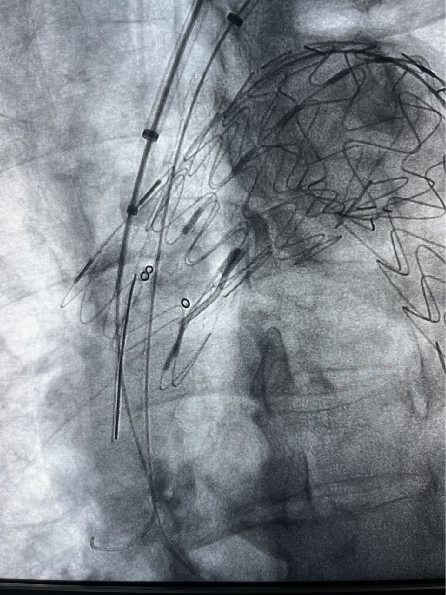

患者男性,51岁,主动脉夹层,通过Futhrough系统完成左锁骨下动脉(LSA)原位开窗重建。术中使用可调弯鞘(Fustar)和破膜系统,DSA显示破膜即刻成功,术后分支通畅,无并发症。

术前造影

穿刺破膜

球囊后扩

术后造影